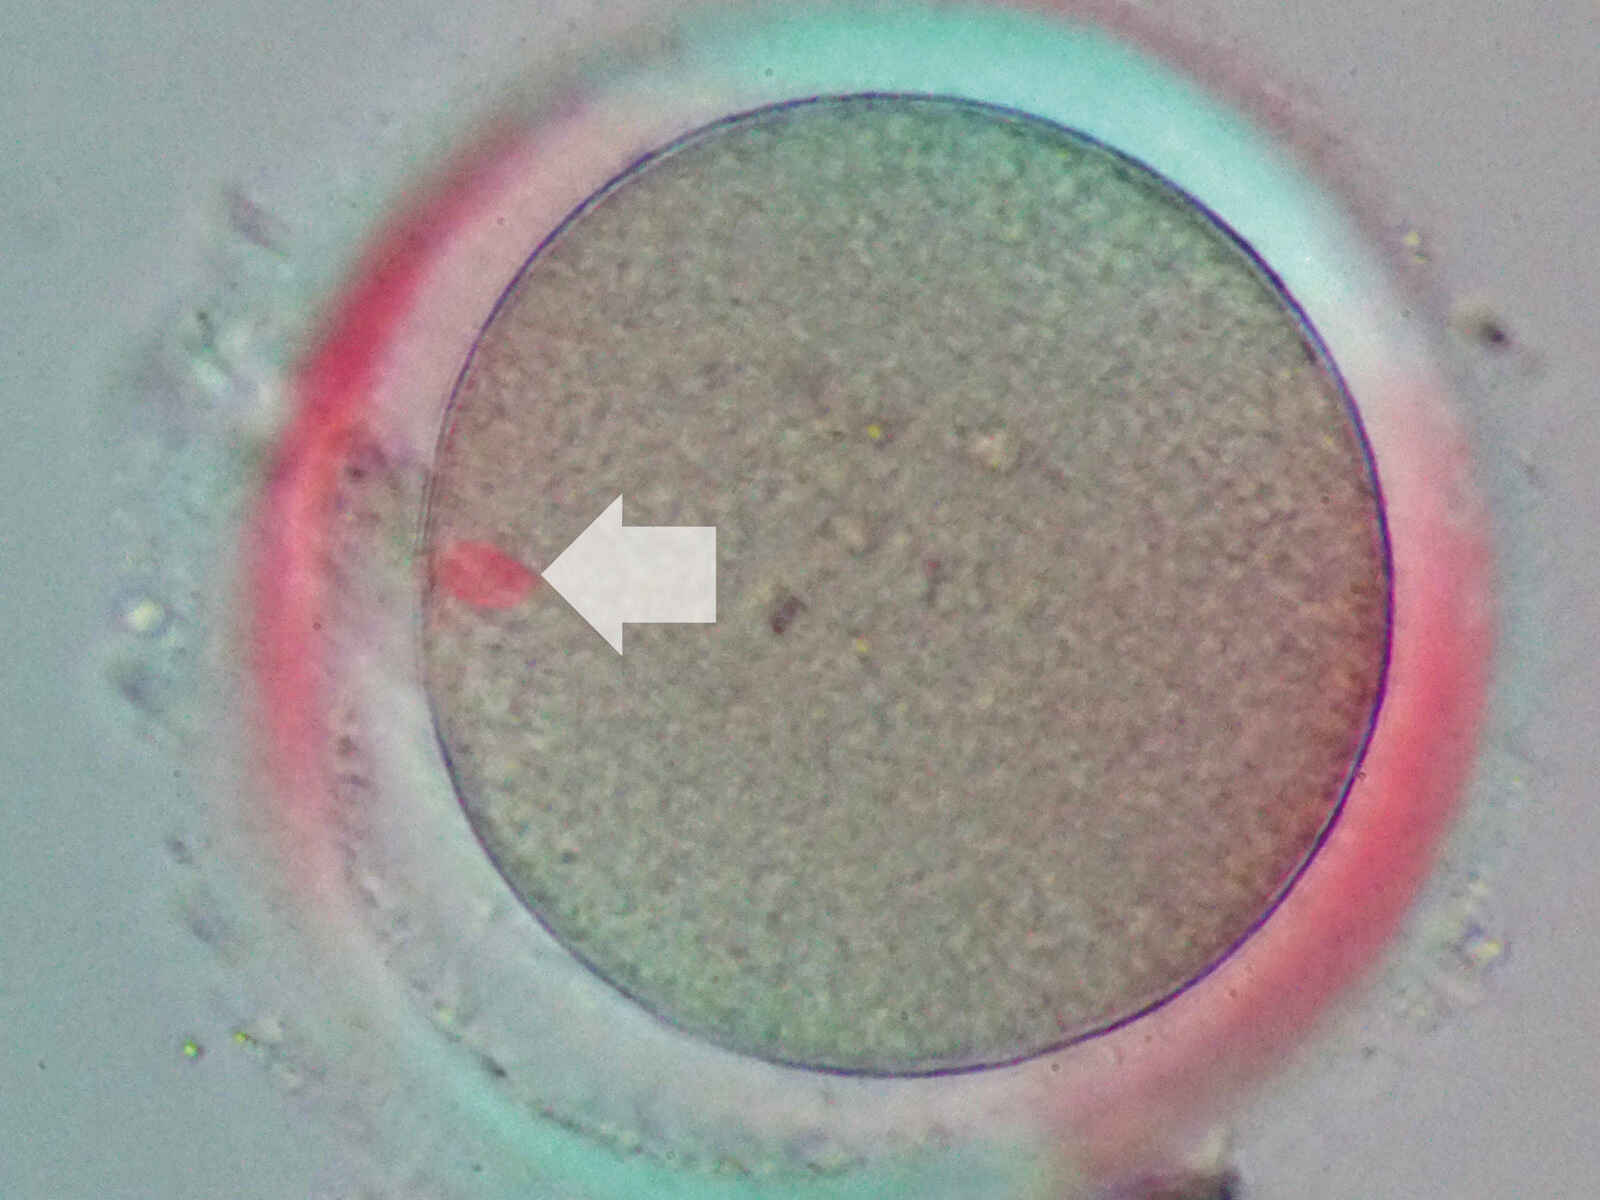

Diese Polarisationslichttechnik ermöglicht eine fein detaillierte Betrachtung von Spindelkörpern für die Eizellenbeurteilung und die Vermeidung von Spindelschäden während der Spermieninjektion.

Der Wechsel zwischen Spindel-Betrachtung und NAMC erfolgt schnell und einfach.

Folgende Objektive sind mit der Spindel-Beobachtung kompatibel: CFI S Plan Fluor ELWD NAMC 20XC und CFI S Plan Fluor ELWD NAMC 40XC.

Bild mit freundlicher Genehmigung von: Reproduction Clinic Tokyo